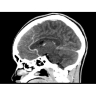

Неврологические исследования

• Выявление инсультов, опухолей головного мозга и травматических повреждений.

• Диагностика заболеваний позвоночника и межпозвоночных грыж.